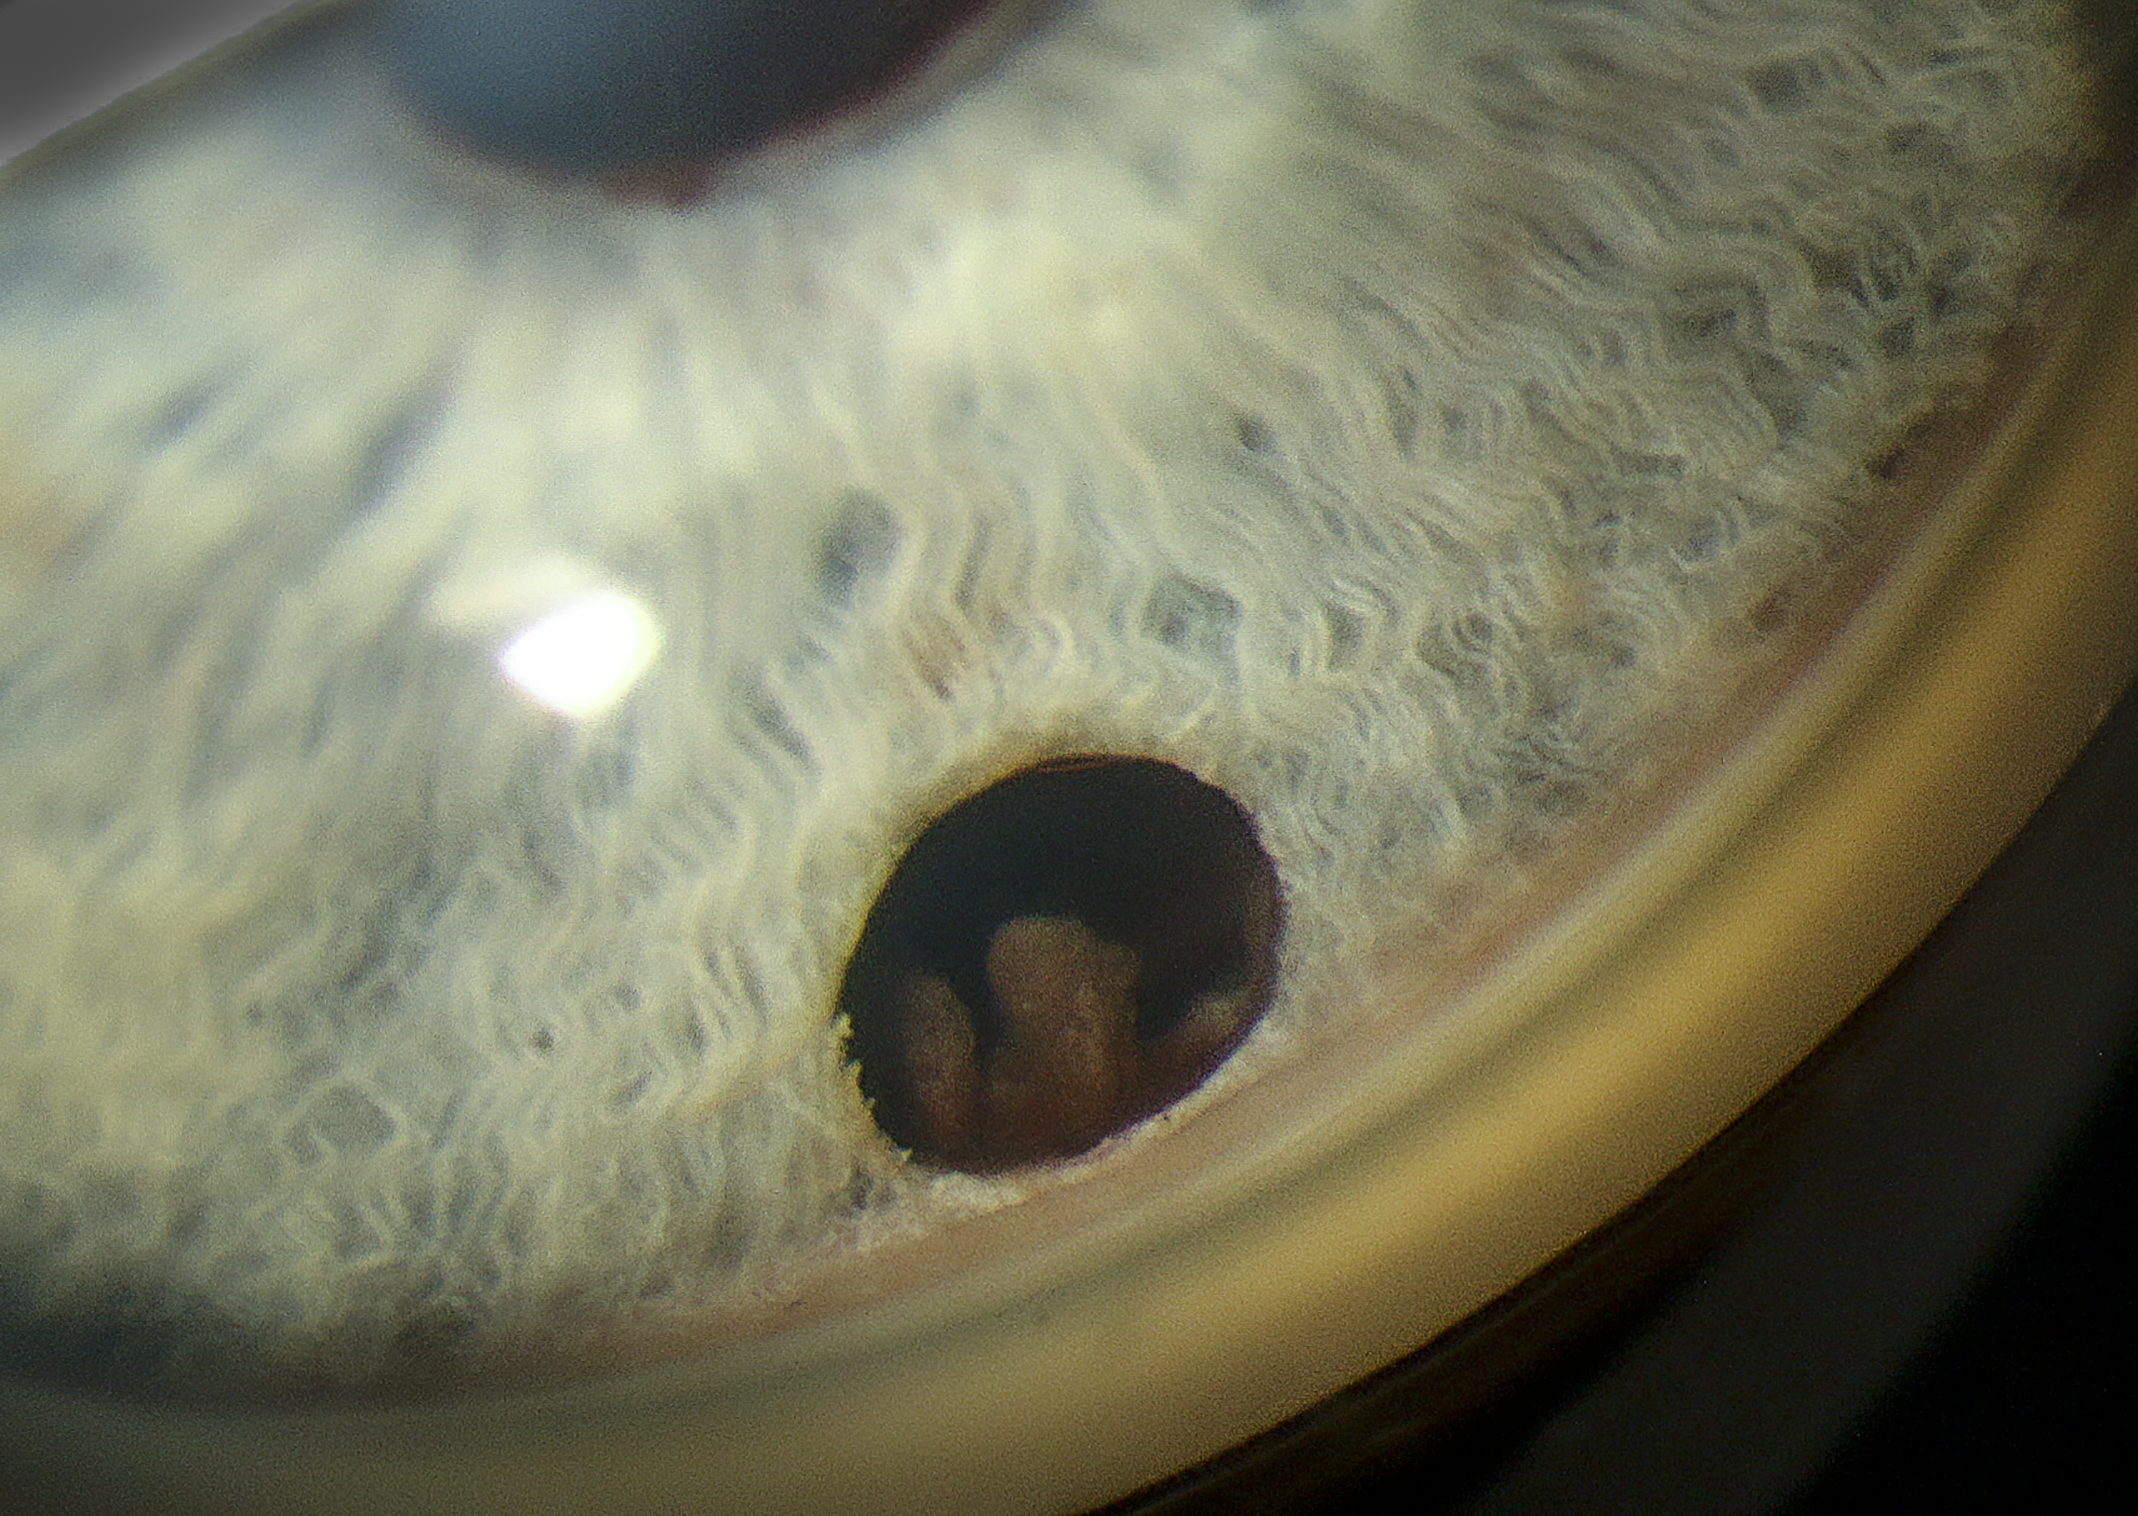

Iridociliary Body Lesion Presented by Judith Gulian, OCT-C This photograph received Second Place, Gonio Photography in the 2025 OPS Scientific Exhibit. Filed Under Cornea OPS Photo